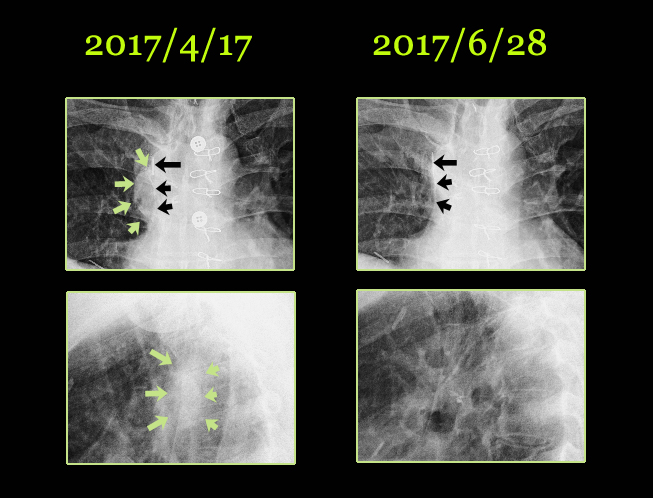

초기에 내원하여서 워낙 환자의 종양이 chest상에서도 약간은 가늠이 되는지라 본원에서는 chest를 찍어서 비교하였다.

환자는 우측 흉벽에 전이가 되어 있고 pleural thickening이 있으며 우측 폐에 화살표로 보이는 mass lesion이 보인다. 옆의 측부 사진에서도 알 수가 있다. chest로 짐작하는 것은 정확하지는 않지만 약물의 방향이나 농도를 측정하기 위하여 쉽게 찍을 수 있는 용이함 때문에 사용된다.

5월 18일 이후부터는 한약과 UFT라는 소음인에게 유효한 항암제를 결합하여 치료를 하였고, 한달여 만에 찍은 6월 28일 사진상 Chest에서는 이전에 보이던 종양이 사라진듯 보이지 않았다.

이를 chest상에서 확대해 보면 아래 사진과 같다. 수술시 철심을 박은 하얗게 보이는 철심(검은 화살표) 기준으로 해서 오른쪽(화면에서는 왼쪽)에 보이던 동그란 부분(2017/4/17)이 소실되어서 보이지 않는다.

물론 X-ray만으로는 다 평가 할 수가 없지만 나는 약물이 확실히 잘 반응한다는 것을 알았고, 식이요법과 운동이 곁들여져야 하는 점을 환자에게 설명하였다. 이 환자는 고군분투하면서 외로운 전쟁을 하고 있지만 좋은 결과는 체질에 맞는 약물 – 그것이 한약이던 양약이던 – 과 운동 등의 부수적인 노력과 환경적 요인도 매우 중요하다. 이 환자는 황토방에서 거주하고 있는데 나는 개인적으로 암환자들에게 황토방과 원적외선은 매우 중요하게 생각하며 가능하면 그런 데 가 있는 것을 권유하는 편이다. 황토방에서 쬐는 원적외선의 효과 또한 우리몸의 림프구를 활성화시켜서 암치료를 도와줄 수 있다고 확신한다. 이러한 황토방요법을 하는 사람과 안 하는 사람들 사이에는 초기 환자라면 모를까 말기 환자에게서는 커다란 차이를 보이는 것을 항상 보아왔다.